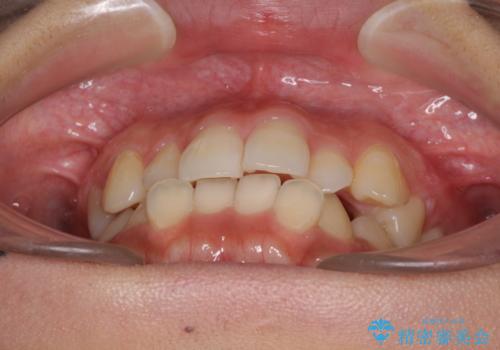

前歯の突出感とデコボコ インビザラインで改善

- 上下前歯のデコボコを気にして来院された患者様です。

インビザラインによる上下歯列の側方拡大と後方移動、IPR(歯と歯の間を削る)にるスペースの獲得により歯列を整えることとしました。